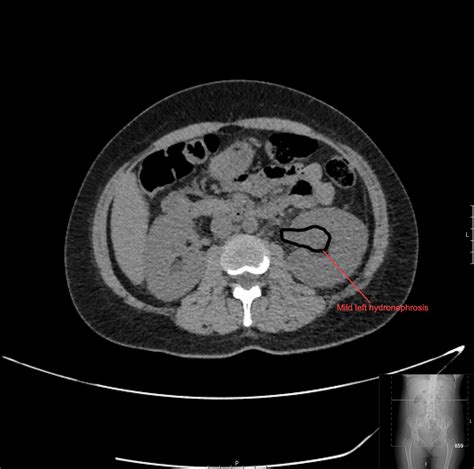

In medical imaging, particularly computed tomography (CT) scans, healthy fat usually appears as a dark, homogeneous, and smooth substance. However, when the body experiences localized inflammation, the delicate, web-like structures supporting the fat—known as the interstitium—become swollen or engorged with fluid. This creates a hazy, linear, or “streaky” appearance on the scan, which is technically referred to as fat stranding.

Essentially, fat stranding is the body’s way of signaling that something is wrong in the immediate area. It is a non-specific finding, meaning that while it definitively proves there is inflammation, it does not by itself identify the root cause. A radiologist must look at the location of the stranding and compare it with other clinical signs to provide an accurate assessment.

When a radiologist identifies fat stranding, they are looking for specific patterns. They evaluate the density of the streaks to determine if the inflammation is acute or chronic. Acute inflammation typically results in fluid-like density, while chronic or scarring processes may look denser and more fibrotic.